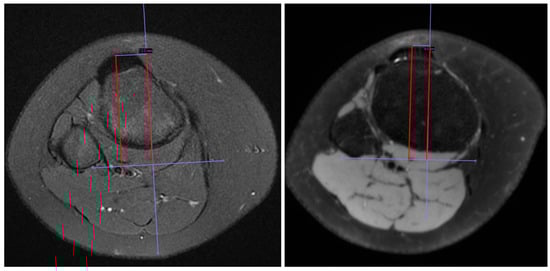

2.2. Radiological Measurement